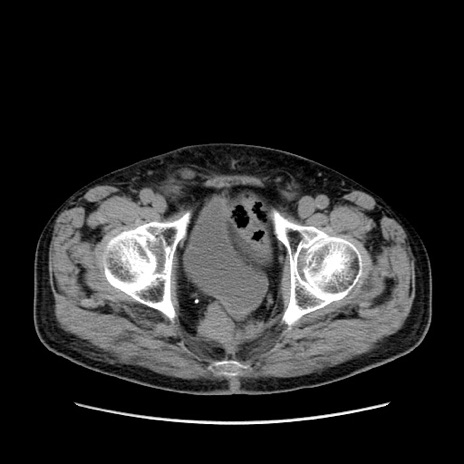

症例24(横断像)

【症例】80歳代男性

【主訴】左側腹部痛、嘔吐

【現病歴】本日早朝より左腹部に痛みあり。昼頃嘔吐認めたため、救急要請。

【既往歴】直腸癌(Mile手術)、胆摘

【身体所見】意識清明、BT 35.9℃、BP 221/93mmHg、SpO2 97%(RA) 、腹部:左ストーマ周囲に限局性の腹部膨隆あり。 膨隆部自発痛・圧痛あり・軟。

【データ】WBC 7700、CRP 0.09